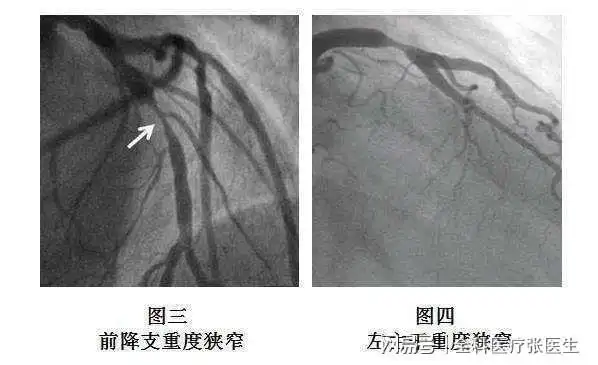

医生通过冠状动脉造影来观察患者心脏中的动脉,能看见动脉中是否有

前因上述症状就诊于心血管病科,行冠脉造影检查提示三支血管重度病变